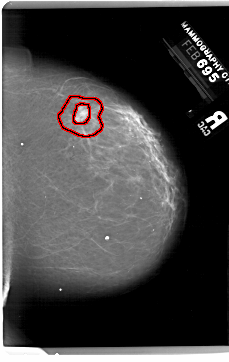

A_1999_1.RIGHT_CC

RIGHT_CC LINES 6871 PIXELS_PER_LINE 4336 BITS_PER_PIXEL 12 RESOLUTION 43.5 OVERLAY

FILE: A_1999_1.RIGHT_CC.OVERLAY

TOTAL_ABNORMALITIES 1

ABNORMALITY 1

LESION_TYPE MASS SHAPE IRREGULAR MARGINS SPICULATED

ASSESSMENT 5

SUBTLETY 3

PATHOLOGY MALIGNANT

TOTAL_OUTLINES 2